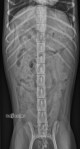

Radiographies colonne thoracolombaire